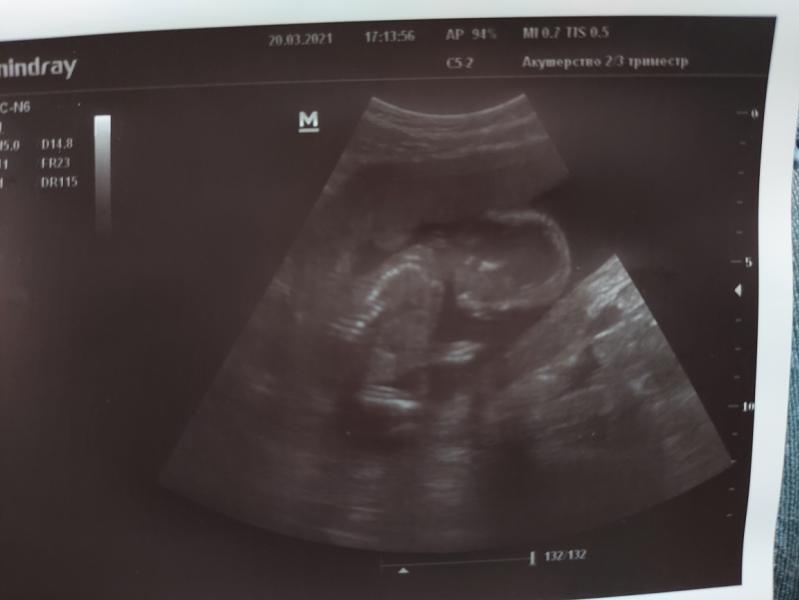

Жаль мальчика нельзя назвать Соней😆 На всех узи дрыхнет, стучащие звуки его не будят)) Весь в мать, абсолютно нечутко сплю😄

Писюн не прятал, нестеснительный совсем)) Так что, если бы не знала пол по НИПТу, сегодня бы он четко подтвердился)